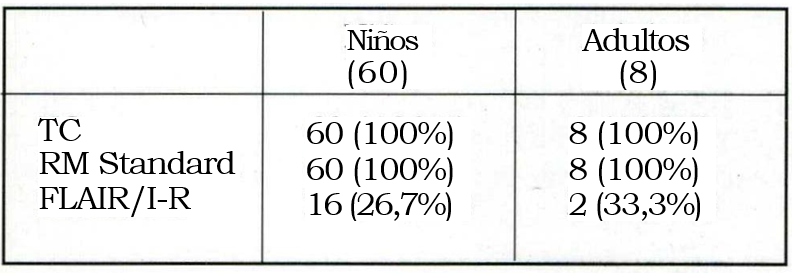

Todos los pacientes fueron estudiados con TAC, RM y EEG de scalp. Desde 1997 todas las IRM incluyen cortes finos, los axiales siguiendo el eje mayor del hipocampo, con FLAIR e Inversión/ Recuperación (protocolo para epilepsias). En algunos pacientes también se efectuó IRM espectroscópica desde 1998. (Tabla 4).

Los exámenes neurológicos realizados se resumen en la tabla 5 y la localización de las lesiones en la tabla 6.

Tabla 4. Imágenes

En un período de 12 años -1988-2000- fueron operados 178 pacientes por epilepsia refractaria (60 niños y 8 adultos), con un seguimiento postoperatorio mayor de 2 años. La edad media de los niños fue de 6 años, la de los adultos 30. La evolución media de las epilepsias hasta su tratamiento quirúrgico fue de 6 años en los niños y 10 en los adultos. Hubo un alto porcentaje de epilepsias sintomáticas (95,6%), acorde con lo comunicado por otros centros. Solamente 4/68 (5,8%) pacientes tuvieron epilepsias idiopáticas (criptogenéticas). De los 60 niños, 50 padecían epilepsias sintomáticas antes de los 10 años de edad, época a partir de la cual se puede considerar terminada la sinaptogénesis cerebral. Dilatar su tratamiento quirúrgico pudo haber llevado a que se perdiera la plasticidad neuronal y la posibilidad de recuperar funciones perdidas por la enfermedad misma o por eventuales déficits que pudieran agregar las cirugías a las que debieron ser sometidos8. En el 62,5% de los adultos las epilepsias comenzaron en edad temprana. Sin embargo, el desarrollo neurológico e intelectual fue normal. También la población adulta se benefició con la oportuna indicación de la cirugía. Mediante la IRM de alto campo desde 1997 se define el llamado protocolo para epilepsia que incluye cortes corona-les en FLAIR e I/R y cortes axiales a lo largo del eje mayor del hipocampo, especialmente útil en las epilepsias temporales. Mediante la IRM espectroscópica se efectuaron estudios volumétricos de los hipocampos. La IRM de alto campo en su modalidad de I/R fue fundamental para mejorar el diagnóstico preoperatorio de las epilepsias, incorporando a los diagnósticos diferenciales la llamada patología dual responsable del fracaso de cierto número de procedimientos quirúrgicos20-26.